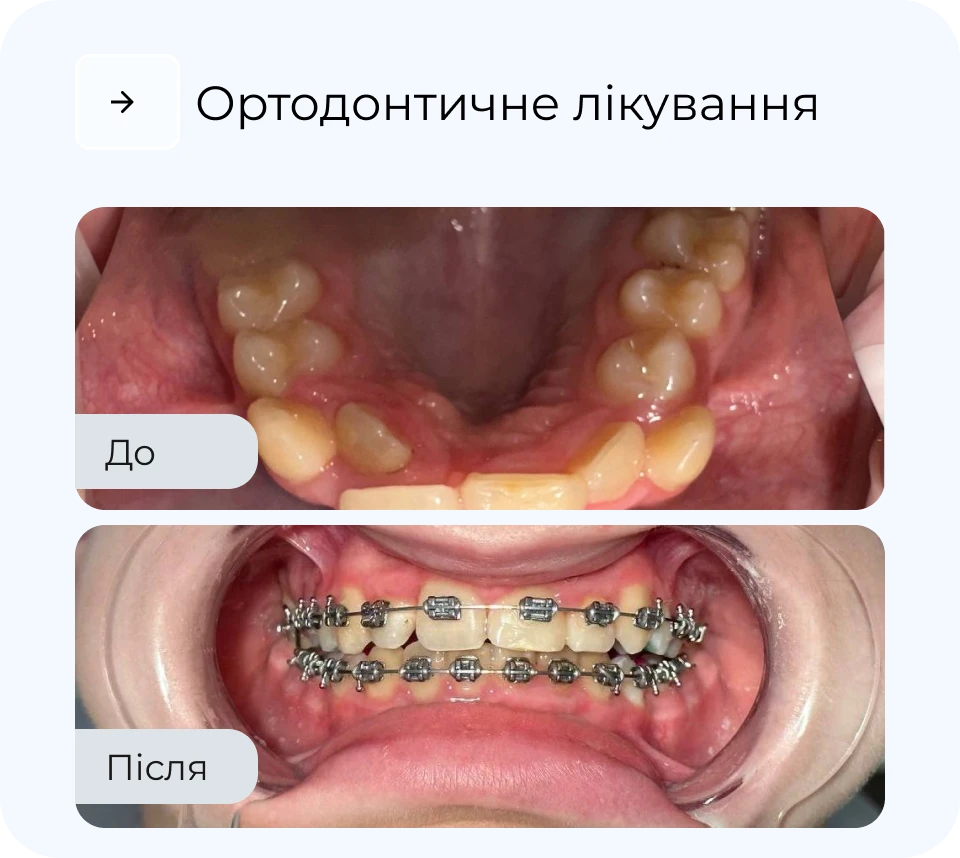

Ортодонтичне лікування дозволяє не лише вирівняти зуби, а й покращити функцію всього щелепного апарату. У MAXI Dent підбирають метод корекції індивідуально — від класичних брекетів до майже непомітних елайнерів. Процес лікування контролюється на кожному етапі, що забезпечує прогнозований результат. Наш підхід — максимально комфортно, естетично і без зайвих втручань.

Наші результати роботи

Результати

*тисни, щоб побачити до/після

Результати

*тисни, щоб побачити до/після